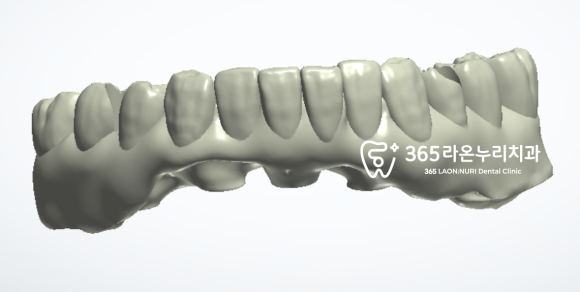

먼저 첫번째 순서는

CT와 구강 스캐너를 이용하여

수술에 필요한 가이드 제작을 하는 것입니다.

임플란트의 뿌리 부분을

픽스처(fixture)라 부르는데,

픽스처가 심어질 공간을 미리 예측하여

제작되는 도움 장치라 생각하시면 됩니다.

자동차도 빠른 길 안내를 위해

네비게이션이 있는 것과 같이

구강 내에서도 픽스처가 심어질

위치, 공간, 깊이를 미리 파악하여

더욱 정교하고 안전한 시술을 할 수 있게끔

도와주는 용도랍니다.

이렇게 생긴 가이드를 이용하면

이미 식립에 관한 예측이 어느 정도 끝났기 때문에

환자는 불필요한 절개를 할 필요가 없어

그만큼 붓기와 통증도 줄어든답니다.

또한 구강 스캔 자료를 통해

임시치아도 미리 제작해두는데요,

픽스처가 치조골 내에서 단단하게

고정되기를 기다리는 동안 사용하실 겁니다.

임시치아를 사용하게 되면

회복 기간에도 사회생활을 하시는데

문제가 없을 뿐만 아니라

나중에 최종 보철이 올라가기까지

어느 정도 턱관절의 위치도 유지해 줄 수 있답니다.